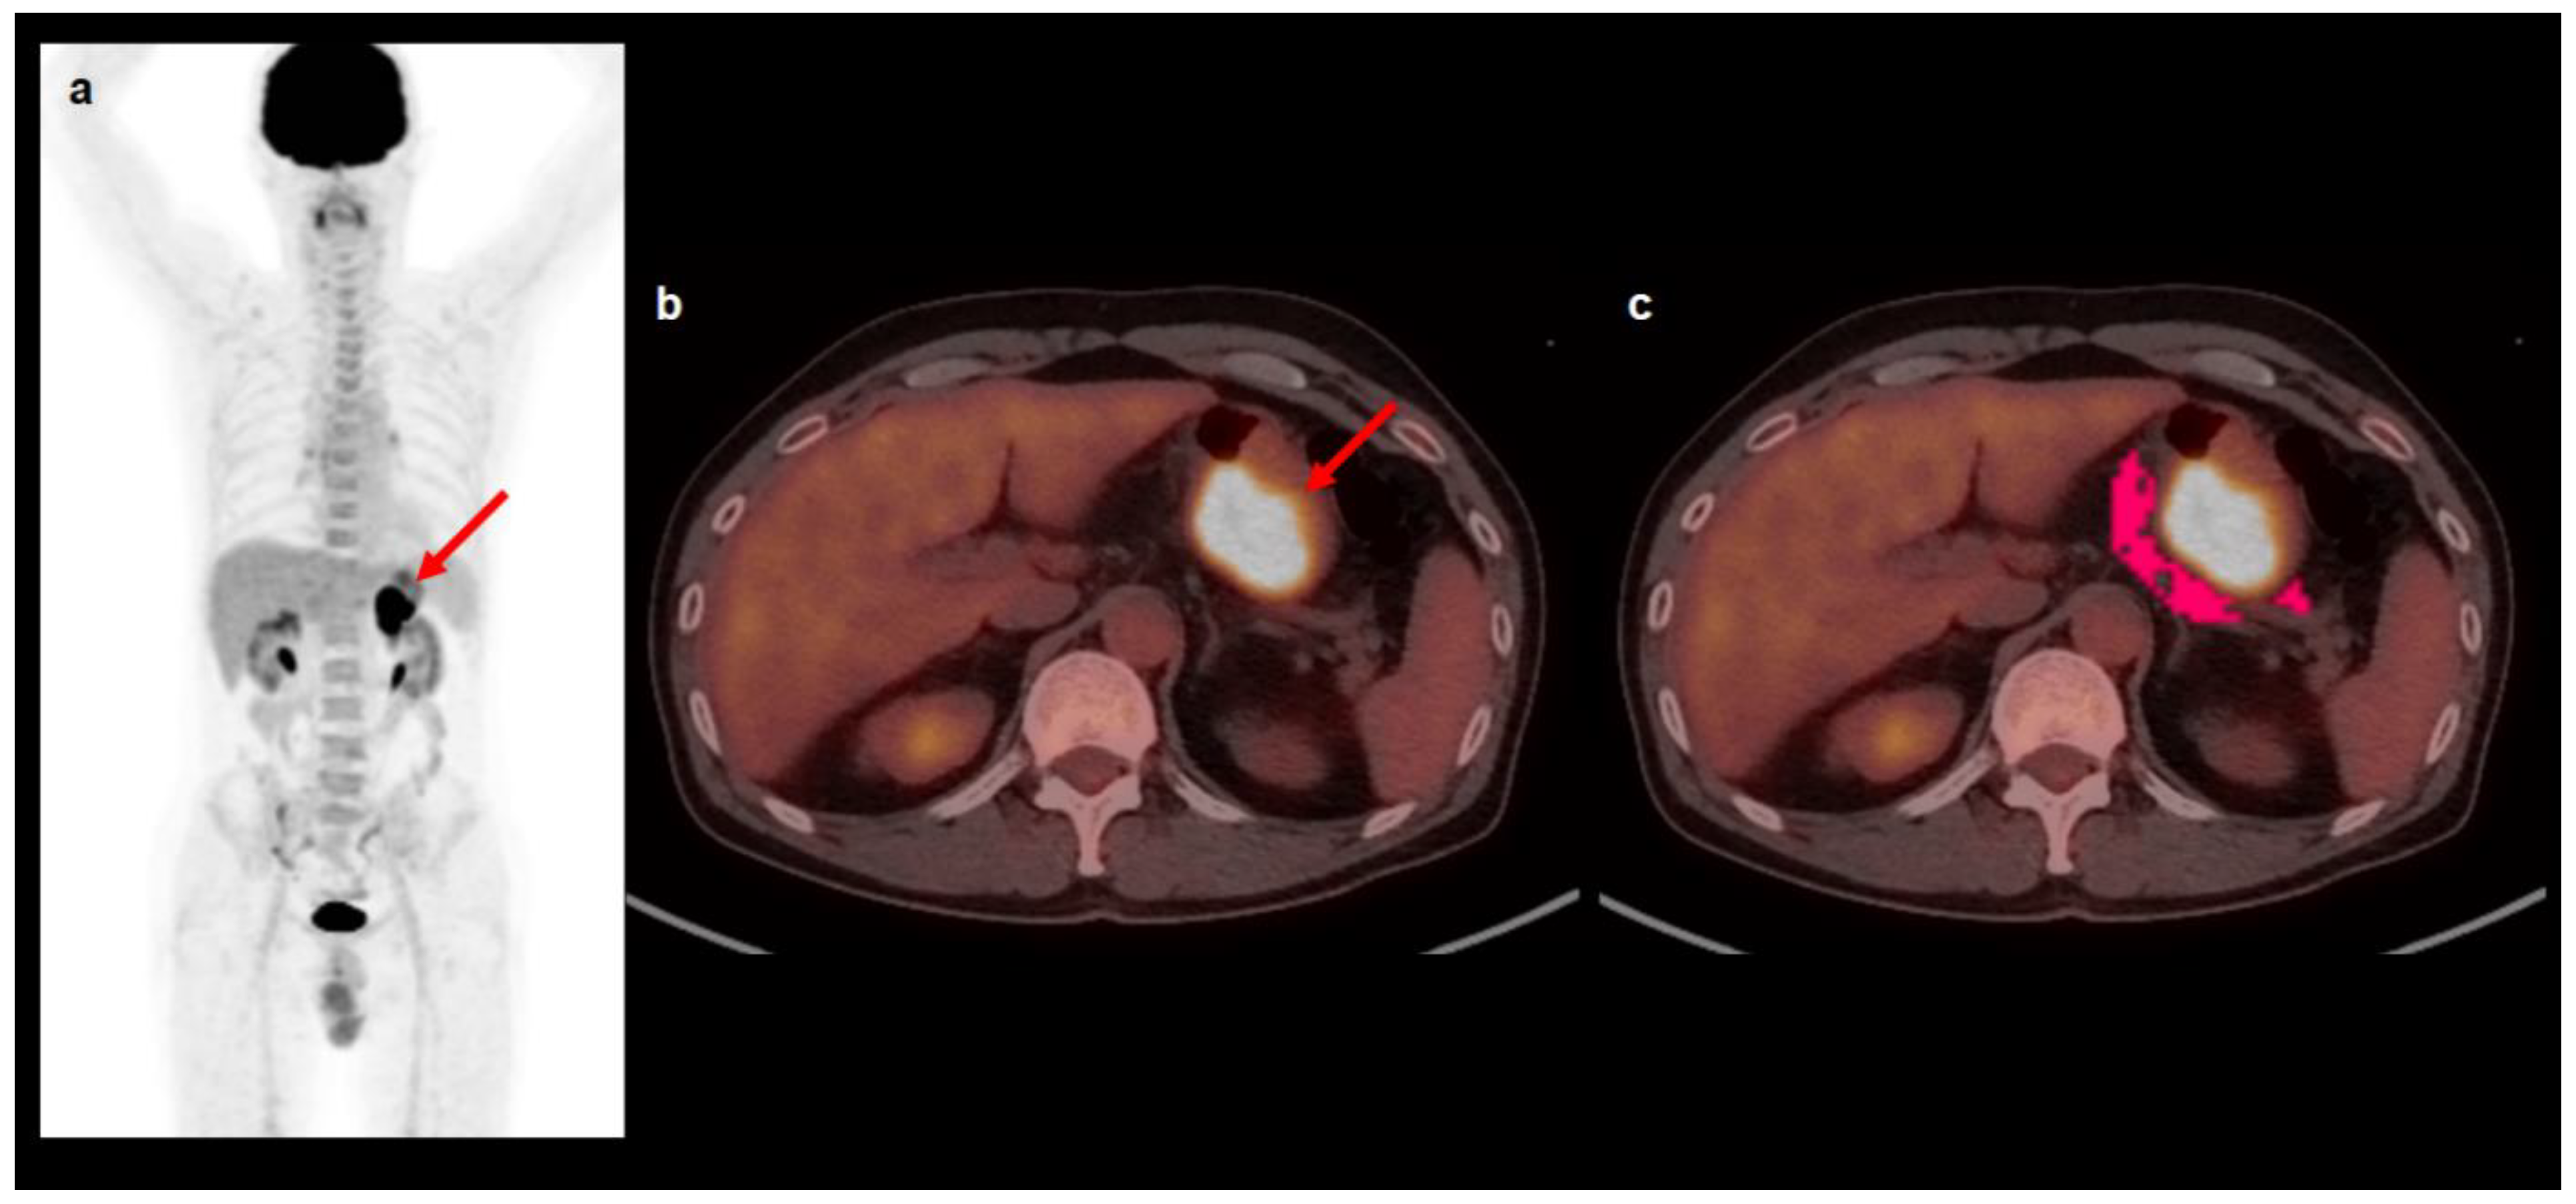

4.2. [18F]FDG PET/CT and Image Analysis